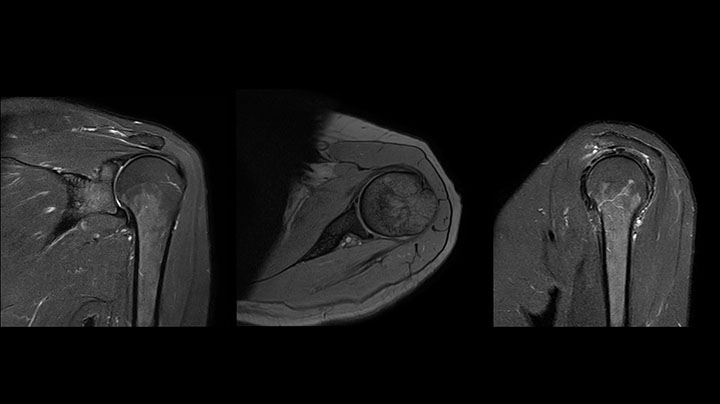

Shoulder MRI with high quality, large coverage

The Prodiva shoulder coil is very flexible and has large coverage, which makes good positioning easier, and that contributes to the superb image quality and high SNR that we get in our shoulder exams.

Scan time 2:55 min, FOV 160 mm,

acq voxels 0.55 x 0.83 x 3.0 mm.

Scan time 4:19 min, FOV 160 mm,

acq voxels 0.55 x 0.80 x 3.0 mm.

Scan time 2:50 min, FOV 160 mm,

acq voxels 0.70 x 0.99 x 3.0 mm.